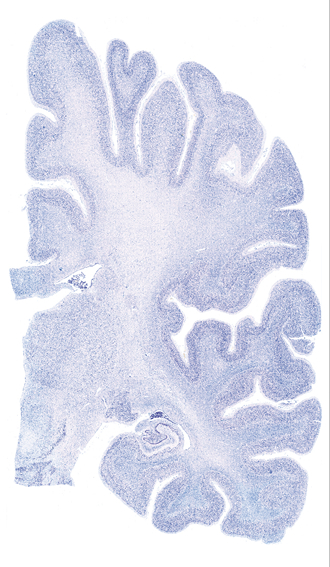

Hi-Resolution Sections · Cells (Nissl Staining) · Virtual Microscopy

Frontal sections (Nissl) from the Atlas Brain:

Slice ID:

r3-0450

Plate NR:

41

Position:

25,2 mm